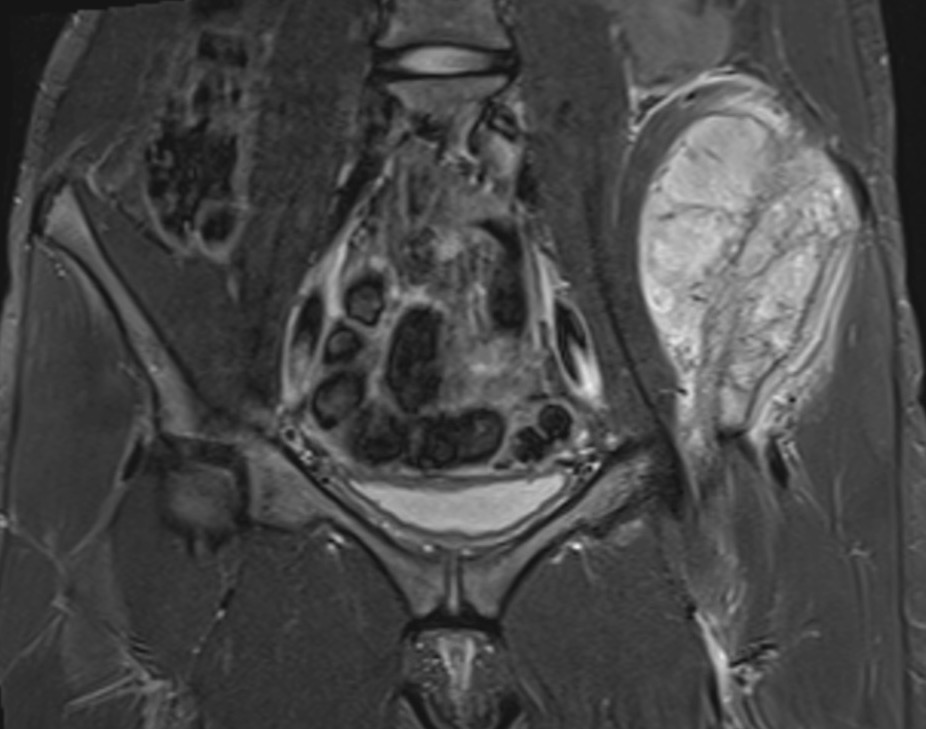

Location

Central

- pelvis (12%)

- scapula / vertebrae / rib / sacrum

MRI

Low signal intensity of T1 / high signal intensity on T2

- intramedullary extent

- skip lesions

Significant soft tissue mass with significant edema

Ewings iliac crest

1. Location

Lower survival with central Ewing's

Brown et al Cancer Treat Res Comm 2022

- 296 / 1152 (26%) patients with Ewing sarcoma of the pelvic bones

- metastasis in 46% at time of diagnosis

- only 29% received surgical resection

- 5 year survival 40%

- 10 year 42%

- higher metastasis and lower survival compared to non pelvic Ewing's